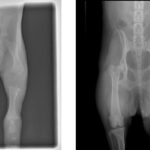

Hieronder zie je een röntgenfoto van een puppy van een paar weken oud en ter vergelijking van een volwassen hond. Het laat echt zien hoe het kraakbeen nog omgezet moet worden in echte botten en goede gewrichten!

De meeste groei vindt plaats tussen de leeftijd van 4 tot 8 maanden, echter in sommige grote / gigantische hondenrassen kunnen de groeischijven open blijven tot 18-20 maanden!